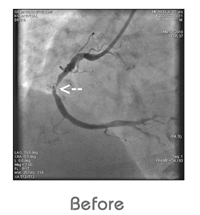

Angiogram

“FIRST TIME” Pukra (Kovai Heart Foundation) introduced World Class Out Patient Angiogram and Angioplasty (STENT).

• “Gold Standard” procedure for coronary artery occlusion, deduction and measurement.

“Walk in Walk out” within 30 Minutes after Angiogram now at KHF (KOVAI HEART FOUNDATION) - Angiogram Centre.